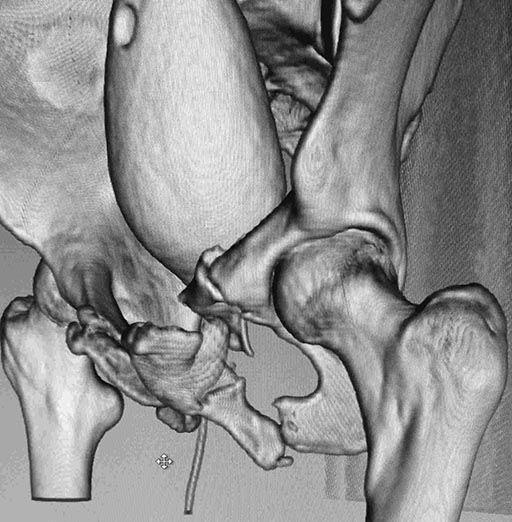

Женщина,21, социальна, без вредных превычек, сбита авто. Кожа не повреждена. Других повреждений нет. Гемодинамически стабильна. травме 2 сут. Планируем спереди открыто через Stoppa, далее сзади крестец и ость закрыто (крестец может через обе массы?). Интересует мнение по альтернативным вариантам и по предложенному (tricks and shots). Заранее благодарен.PS Только часть скринов с body scan, один с контрастированием пузыря.

Постоп. Верхняя ветвь возле шейки мочевого пузыря, нижняя так же где-то глубоко в мышцах, ротирована. Обе практически лишены кровоснабжения. лонное сочленение фактически свободно лежащее, справа почти целое, но ветви сломаны возле него. Слева часть лонного сочленения цела на 2/3. интраоперационно подвижность правой половины таза. Постоп все стабильно, но все же планирую дополнительно провести IS винт справа.